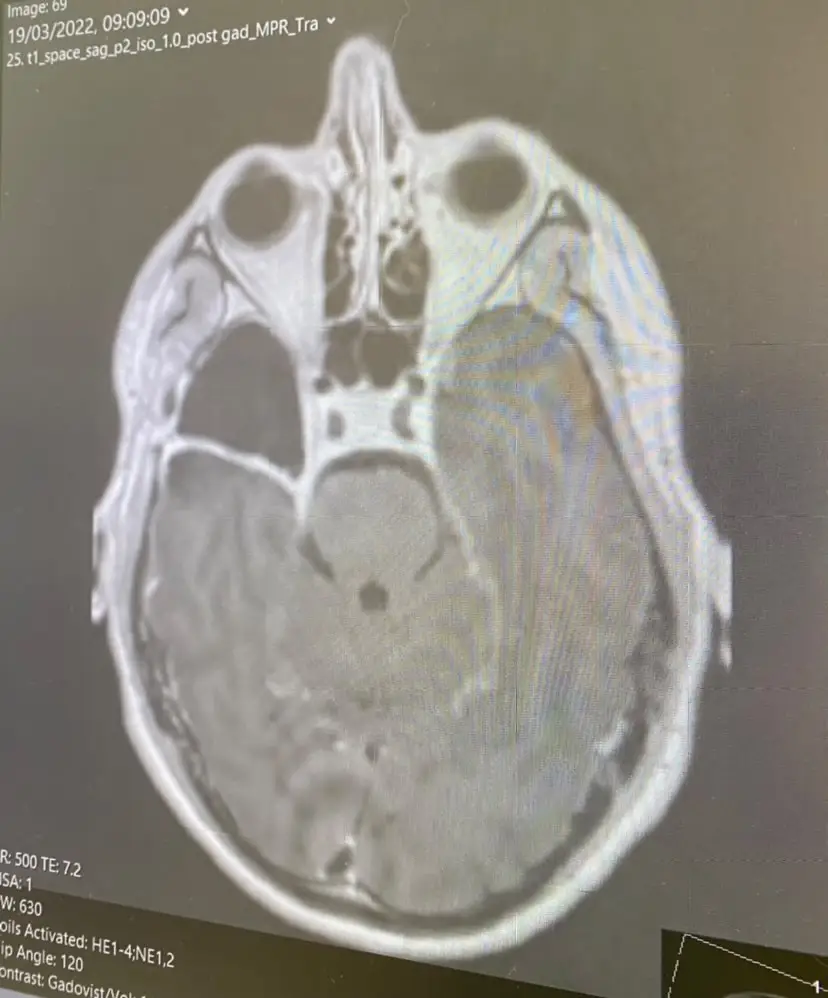

The scent left him convinced his house was on fire, but Anna couldn't smell anything and consequently encouraged Alex to go and see his doctor. After being referred to an ear, nose and throat specialist, Alex had an MRI scan which revealed a mass on his brain.

The 34-year-old underwent surgery and learned he had a brain cancer known as glioblastoma. It's the same disease which took the life of former MP Tessa Jowell, whose death inspired her daughter Jess Mills to co-found the Tessa Jowell Foundation to fund brain cancer research.

Speaking to the Sun Health about his diagnosis, Alex explained: "The horrible thing about glioblastoma is that it grows with microscopic tendrils, so while my surgeon was able to get what he could see — and an eighth of my entire brain too — there’s no guarantee it won’t come back."

The surgeon removed a 'huge chunk' of tissue surrounding the tumour, which made up about a quarter of the right side of his brain, but was told the left side would 'pick up the slack' lost by the operation.